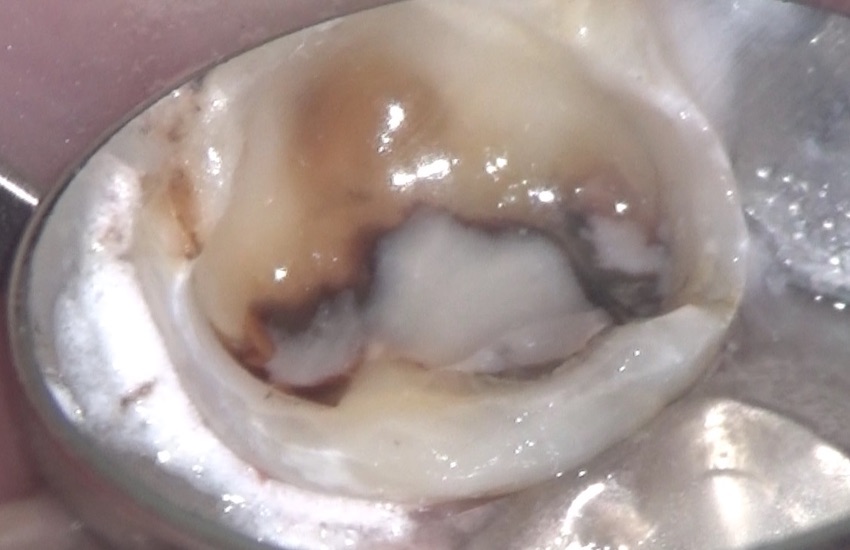

これが、虫歯になっている歯の最初の状況。

虫歯を取り除いています。